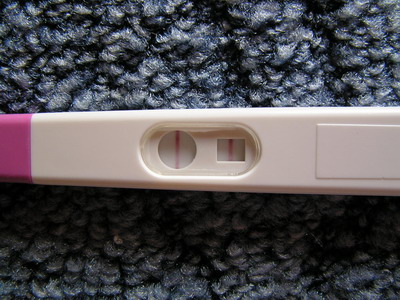

2008. május 13.

2008. május 13.  2008. május 16.

2008. május 16.  2008. május 19. 6+4

2008. május 19. 6+4